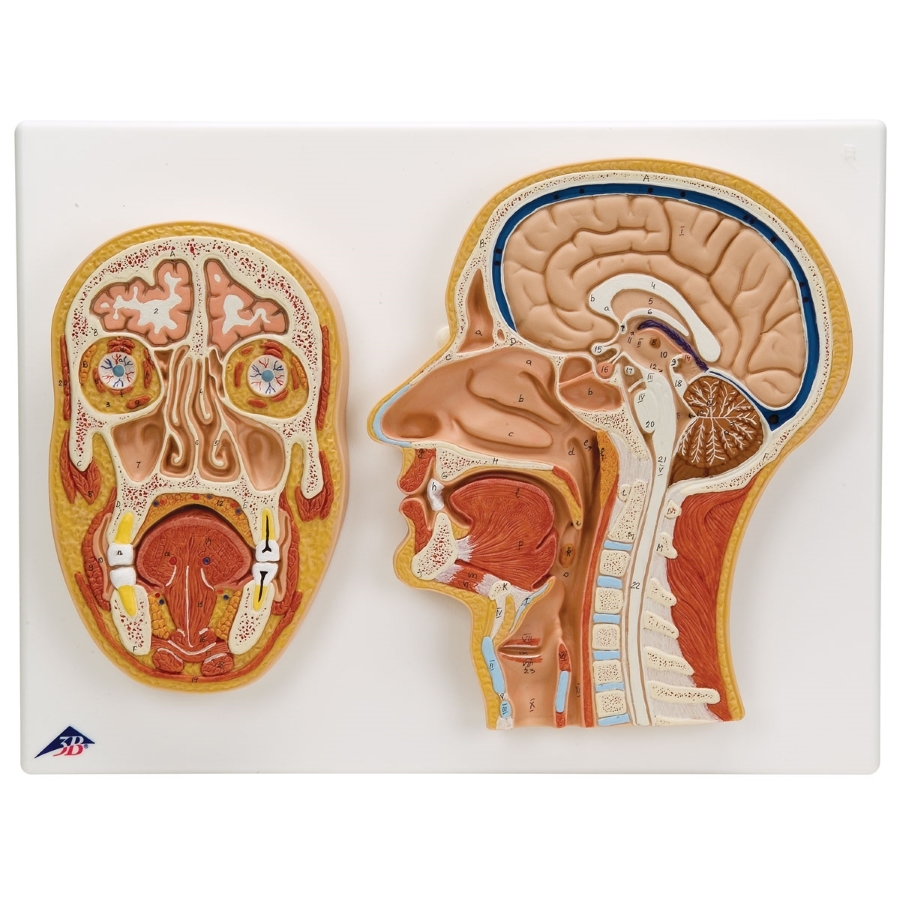

Anatomical Median and Frontal Section of the Head Model

Anatomical Median and Frontal Section of the Head Model Anatomically Correct Head Models See here for assembly video:. the anatomy of the human skull. This is a model of the human (homo sapiens) skull. explore our diverse range of human skull and head anatomy models and charts, offering detailed representations of the skull, cross. with so much going on upstairs, it's important for doctors and students to understand the contents. Anatomically Correct Head Models.